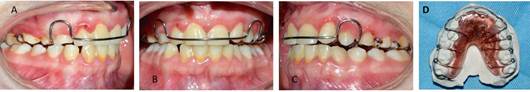

El diagnóstico integral con enfoque de riesgo es paciente género femenino, 16 años, potencialmente cooperadora, sin riesgo social, con riesgo biológico general, dentición permanente, gingivitis generalizada asociada a condición sistémica, lesión compatible con fibroma irritativo en flanco lingual izquierdo a nivel de 3.7. (Figura 2), caries oclusal profunda en diente 4.7, clase III esqueletal, biotipo braquifacial, perfil anterior anteinclinado, clase III canina y molar bilateral, overjet y overbite disminuidos, persistencia de dientes 5.3, 6.3 y 8.3, caninos permanentes con anomalía de tamaño por diente pequeño, apiñamiento dentario severo en maxilar y moderado en mandíbula, líneas medias dentarias no coincidentes, dinámica mandibular normal, respiración mixta, incompetencia labial, anteposición de cabeza. Se determinó la persistencia de tres caninos temporales, pero debido a la alteración de forma de los caninos definitivos se cuantificó éstos últimos como supernumerarios (Figura 3).

La planificación del tratamiento de Ortodoncia comprendió un tratamiento bimaxilar de compromiso con exodoncias de los dientes 1.3 - 6.3 y 8.3. El plan de tratamiento inicial comenzó con el uso de aparatología Multibrackets MBT .022 con bandas en molares superiores e inferiores. La paciente no consentía sesiones de más de 15 minutos, realizando la instalación parcial superior, a modo de adaptación al tratamiento de ortodoncia, para posteriormente continuar con instalación de arcada inferior. Se derivó a Odontopediatría para las exodoncias de los dientes 1.3 - 6.3 y 8.3. Luego de cuatro meses, la cuidadora refiere que la paciente descementaba intencionalmente los brackets con un lápiz. Si bien se realizó la reposición de éstos, el mal hábito persistió, por lo que se adoptó como alternativa de tratamiento instalar botones, con el objetivo de generar cupla y desrotar los incisivos superiores, continuando con la etapa de alineación y nivelación (figura 4). El mal comportamiento de la paciente persistió en el tiempo, pero aun cuando tenía indicación de retiro de los aparatos, debido a su conducta y la permanente gingivitis, se determinó modificar los objetivos terapéuticos propuestos en un inicio del tratamiento, dando prioridad a lograr el cierre del espacio provocado por la exodoncia del diente 6.3 para la alineación de la arcada superior. Por ellos, se suspendió la instalación de brackets en la arcada inferior y se decidió confeccionar bandas individuales para los dientes que requerían mayor alineación, utilizando como secuencia de arco un Niti Natural .014 y .020, junto con un SS .020 (Figura 5)